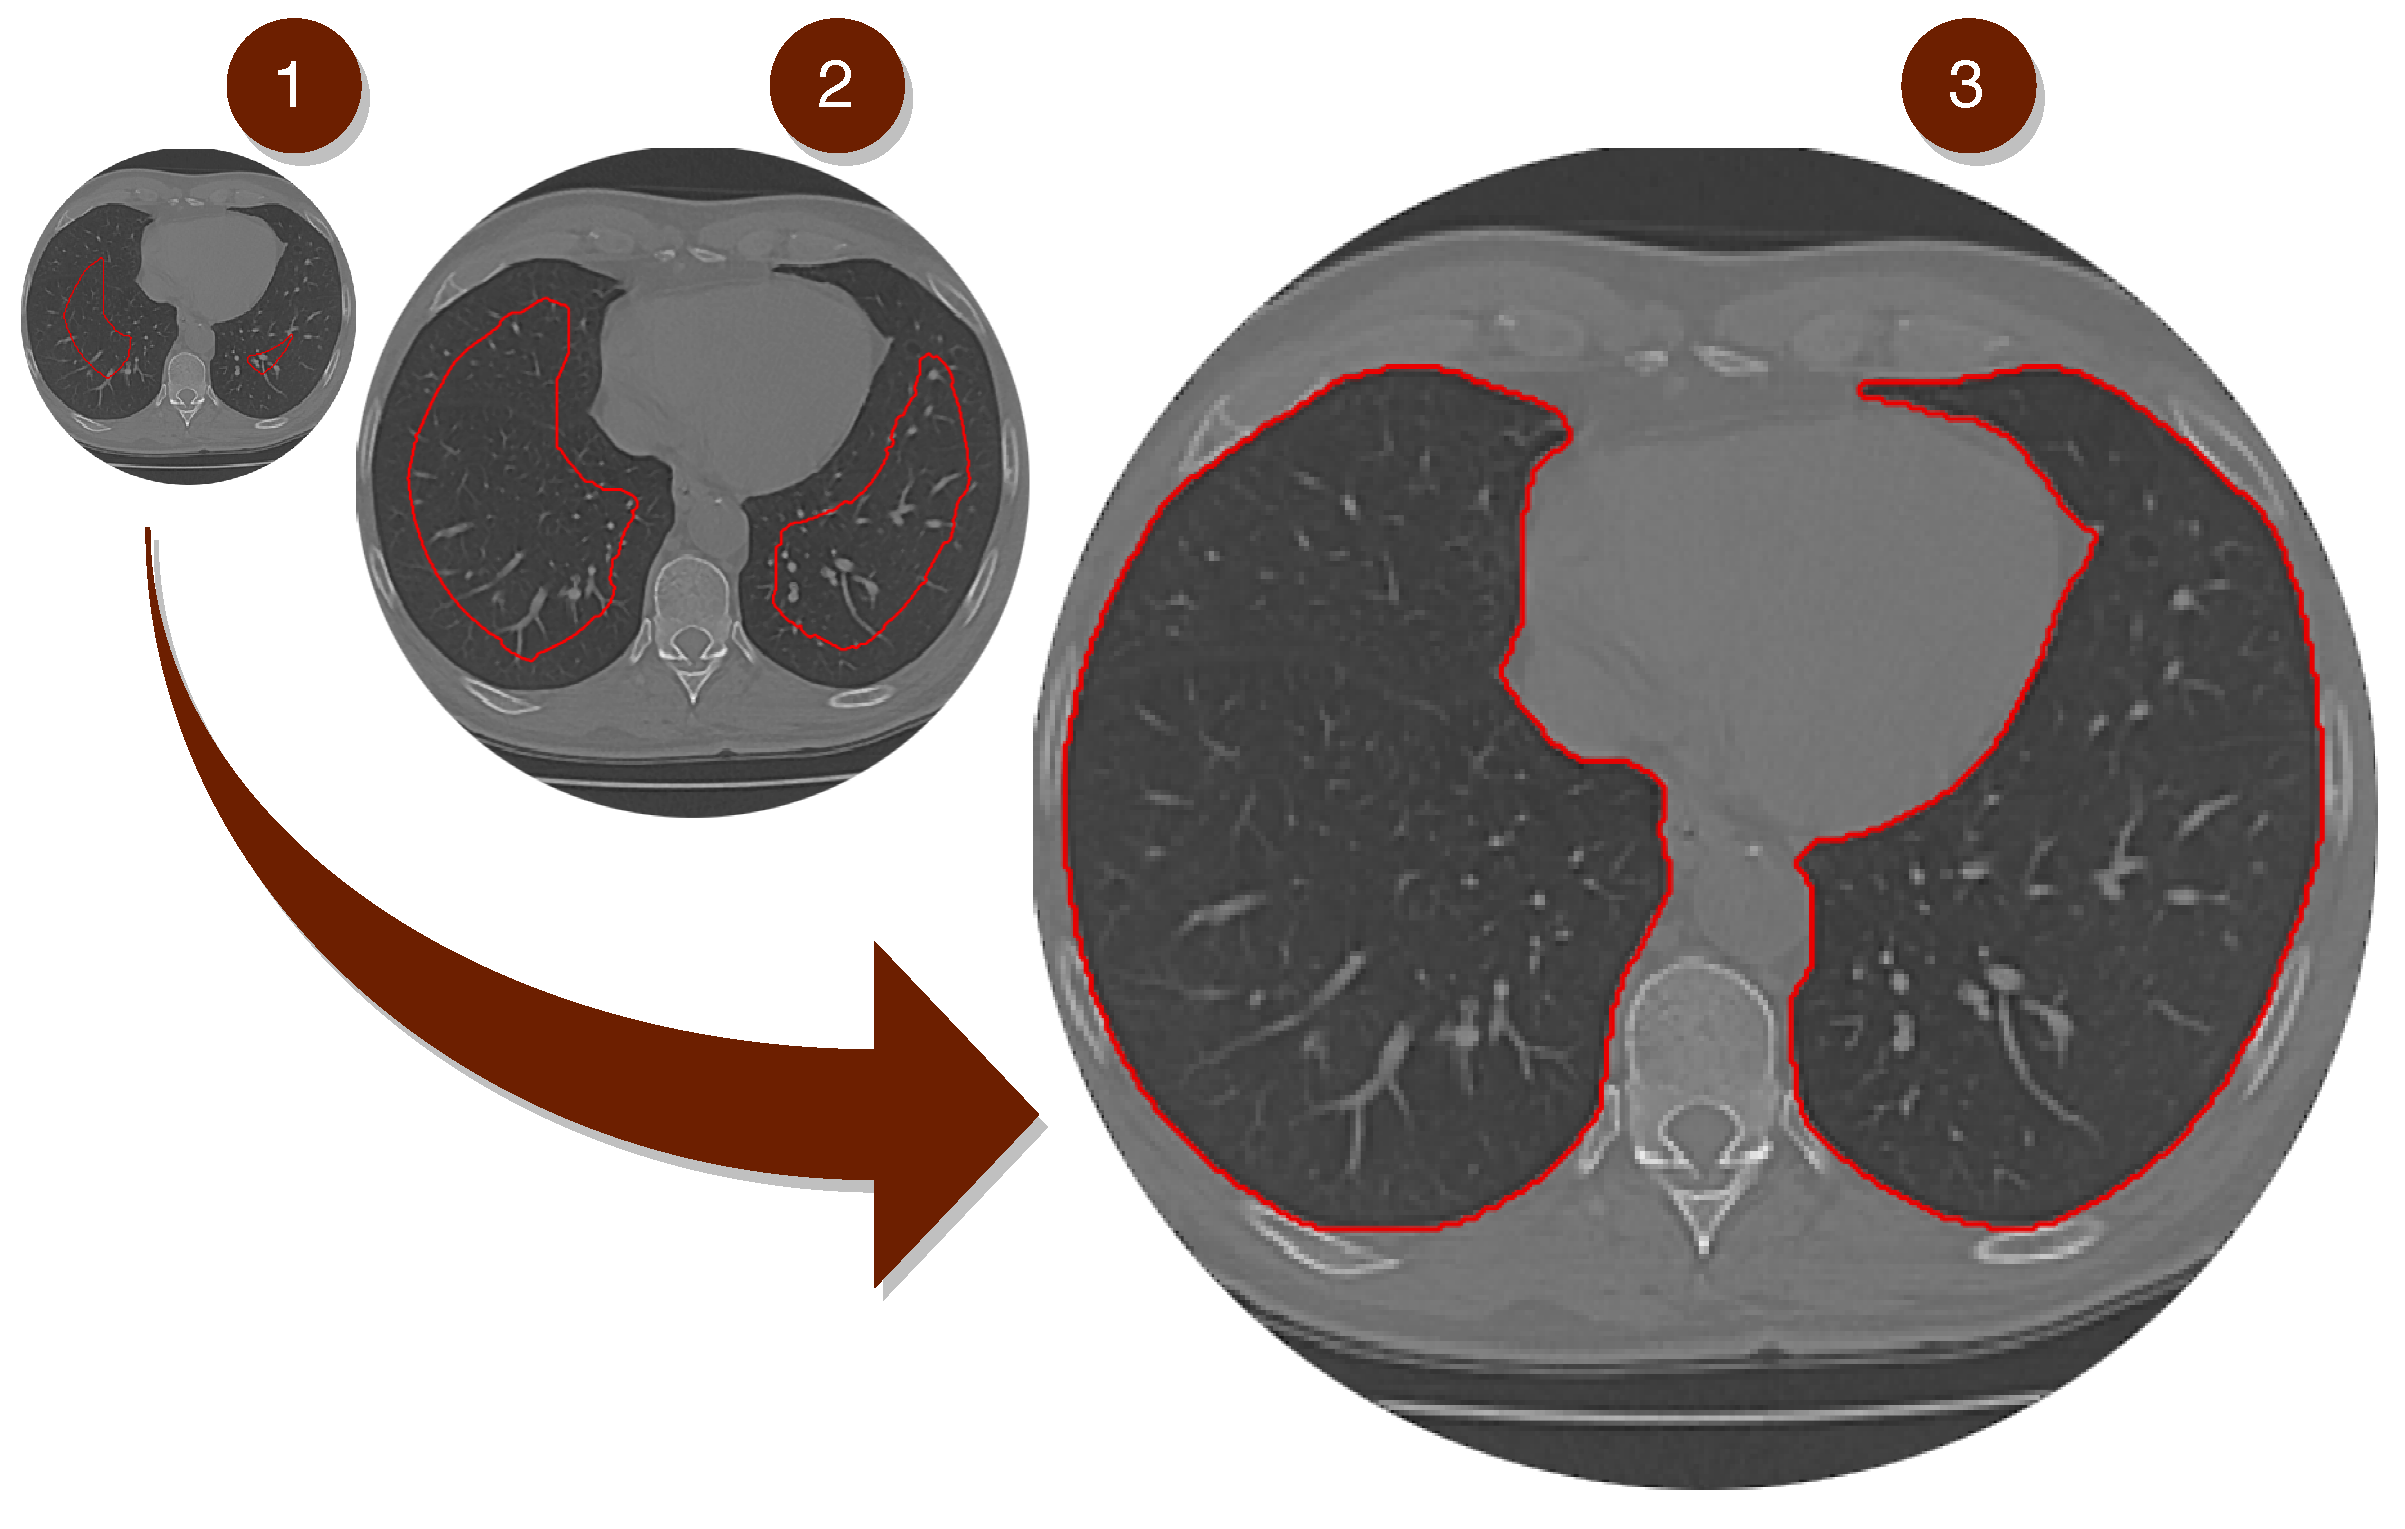

The second phase of the proposed model is shown in Figure 4. A lung map is created in Step 2, using the Mask R-CNN network to detect the lung region. After this process, the model uses fine-tuning to detect the edges of the lung region by readjusting it to the lung wall, as clarified in Steps 3 and 4.

Figure 4.

This Infogram represents the second phase of the proposed method. The image (INPUT), the result of the process of the first STEP 1 phase, is the input to the Mask R-CNN network. In (STEP 2), the model based on deep learning creates a map of the proposed region belonging to the lung represented by the image (STEP 3–Mask R-CNN OUTPUT). And finally, Transfer Learning process using Parzen’s Window method in (STEP 4) finishing with the segmentation of the lung region.

In Figure 4, before starting the transfer learning process stages with our model for segmentation of lung CT, training of the model based on the R-CNN mask network is performed, designed to detect the area corresponding to the lungs. The set is trained based on the ground truth, as it uses only images already segmented by a specialist doctor. The knowledge generated by the Mask R-CNN model is stored at the end of the training.

4.2.2. Second Phase—Segmentation

In Step 2, as shown in Figure 4, the model receives the image from the previous phase (Step 1) that contains the lung image. If the classifier does not find the lung in the CT image, the process already ends in phase 1 (Step 1) automatically. In the case of detection of the lung image, the model proceeds to Step 2. In (STEP 2), the Mask R-CNN network is used to create the lung map of the input image of the proposed model. After making the pulmonary map in (STEP 3), the fine-tuning process using the Parzen window in the (STEP 4) method using the Mask R-CNN network’s weights is followed. And finally, after STEP 4 with the result of pulmonary segmentation.

In STEP 2 of the model, the lung tomography image is processed with the R-CNN Convolutional Neural Net Mask. In the image (INPUT), the segmentation process based on our method is initiated with the insertion of the lung CT image in the model, process image from previous phase 1. In STEP 2 of the model, the lung tomography image processed with the Convolutional Neural Network Mask R-CNN, a network built in order to classify different types of objects with attributes stretched by their wide range of layers. The classification process is divided into two phases: In the first phase, the possible region of the lung’s existence is demarcated with a bounding box. During the second phase, the bounding box’s pixels are classified as belonging or not to the pulmonary regions. It is worth mentioning that the attributes used are selected based on the network architecture. Then, after the pixels are classified as belonging or not to the region of interest, the network performs the construction of the region of interest through the pixels classified as belonging to the pulmonary region.

After STEP 3 of the model, the Mask R-CNN classifier detects the region of interest parallel to its classification and detection process, applied over the lung tomography image pixels. The output of this classification is a demarcated (detected) region. This region, called a mask, is used in the second stage of operation of the proposed method: the mask can be considered as a kind of segmentation through the detection of the object, detailed its functioning in Section 3–A. However, the results are not entirely satisfactory, as the method captures by detecting the object as a kind of segmentation bypassing the object showing its location in the image.

In Step 4, to improve the detection contour for high-level segmentation, the result generated by Mask R-CNN has its dimensions reduced so that it can be used as an input parameter in the Parzen window function, being the starting point for the meeting of the edges of the lung. This decrease can be demonstrated in the Equation (1). The Parzen window function estimates the probability that a particular pixel belongs to a specific region or not. This estimation is performed by calculating a probability density function. The Gaussian kernel function smoothes the reallocation of the pixels marked as belonging to that region. The image generated by the Mask R-CNN is used as an input parameter for the Parzen function. The probabilistic calculation is performed on the image of the brain’s gray matter, more precisely in the Injured region.

Thus, with the overlay of the result generated by Mask-RCNN on the original image of the CT scan of the lung, the new segmentation region is formed. As shown in STEP 4, this segmentation region is stable, as it tends to grow or decrease its edges according to the results of the probability calculations performed by the Parzen window function, found in the Equation (2), and the main kernel function used is the Gaussian function, composed of the formula: